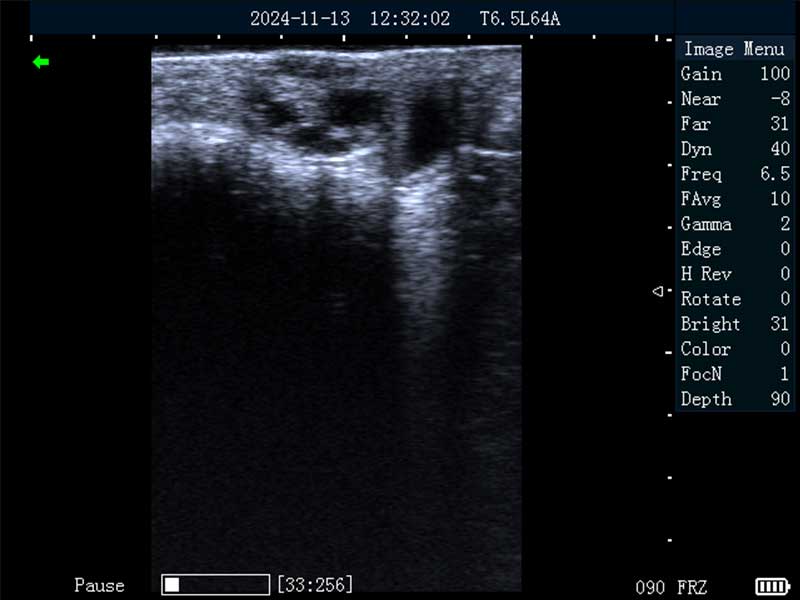

牛卵巢